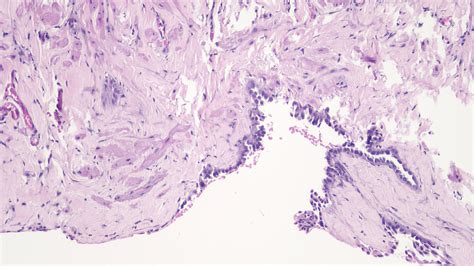

A testicular cyst, commonly referred to as an epididymal cyst or a spermatocele when it originates from the epididymis, is a fluid-filled sac that develops within the scrotum. These cysts are typically non-cancerous and do not spread to other parts of the body. They can vary in size, ranging from very small, barely palpable bumps to larger, more noticeable fluid collections.

• Spermatoceles: These are painless, fluid-filled cysts in the epididymis that contain sperm.

• Epididymal Cysts: Similar to spermatoceles but typically contain clear, serous fluid rather than sperm.